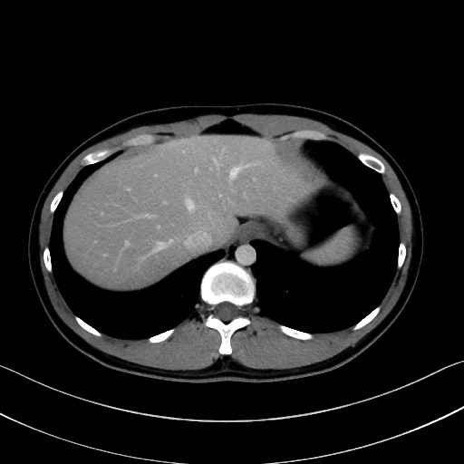

【症例】20歳代 男性 スクリーニング

■起始:典型的には腹腔動脈幹(celiac trunk)から左胃動脈・総肝動脈とともに三分岐し、脾動脈は左後上方へ向かう。

■走行:膵上縁または膵実質背側を蛇行しながら左方へ進み、膵尾部近傍で脾門へ至る。蛇行の程度は個体差が大きい。

■終枝:脾門部で複数の終末枝に分かれ、上極・下極枝や脾門枝群を形成する。胃短動脈群や左胃大網動脈はしばしば脾動脈から分岐する。